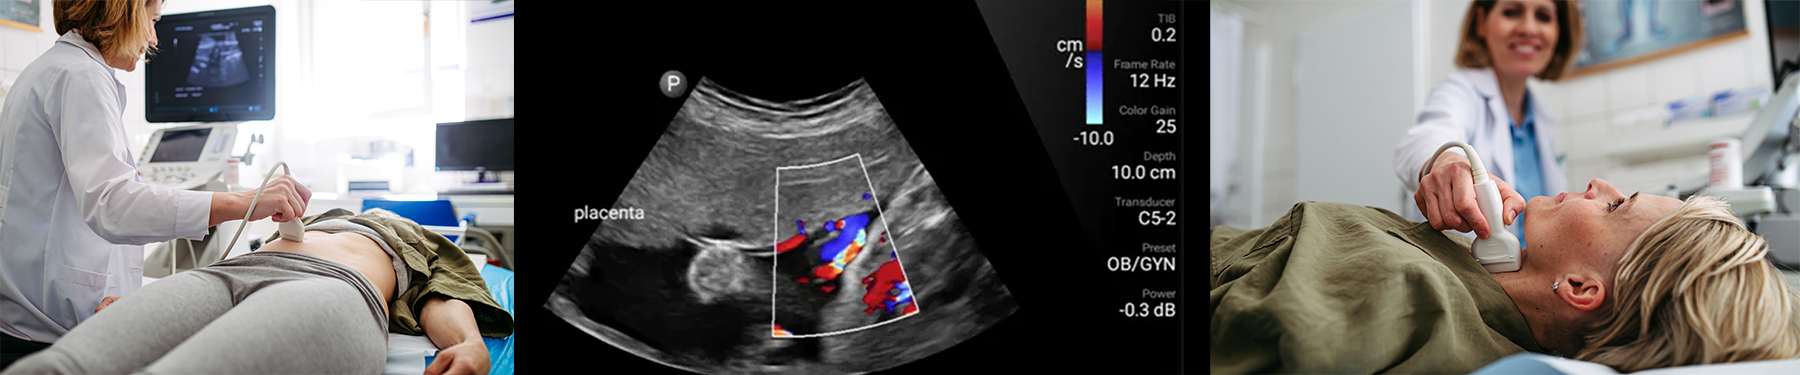

Ultrasounds, or sonograms, are performed at every ZP location. Our state-of-the-art high resolution ultrasound systems obtain images of internal organs and other soft-tissue structures inside the body. Our certified medical sonographers are dedicated to taking the time necessary to provide quality service to all of our patients. Ultrasound is a safe and painless test that uses high frequency sound waves to produce images. The sound waves cannot be heard or felt. Still and moving real-time images can be captured during an ultrasound.

To produce images, a transducer, or probe, is placed on your skin and pulses of sound waves are sent through your body. As the sound waves pass through the body, they produce echoes which are received by the transducer and sent to the computer. The echoes are analyzed and converted into images, which in turn create real-time pictures on the monitor. This helps to determine the shape, size, and composition of organs and tissues.

Since ultrasound records images in real time, it is especially useful for examining blood flow and guiding needle biopsy procedures.

The ultrasound technologist will place the transducer gently on your skin where the gel was applied and move the probe around slowly. Changing the direction or the angle of the probe allows the sonographer to get the best possible images of the organ or tissue being examined.